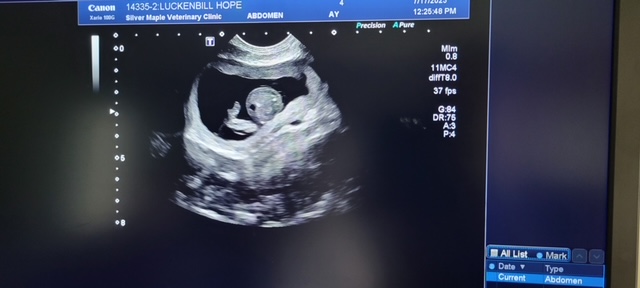

Breeding Services

When it comes to breeding, we understand the need to have a close relationship with your veterinarian. We provide the following services: